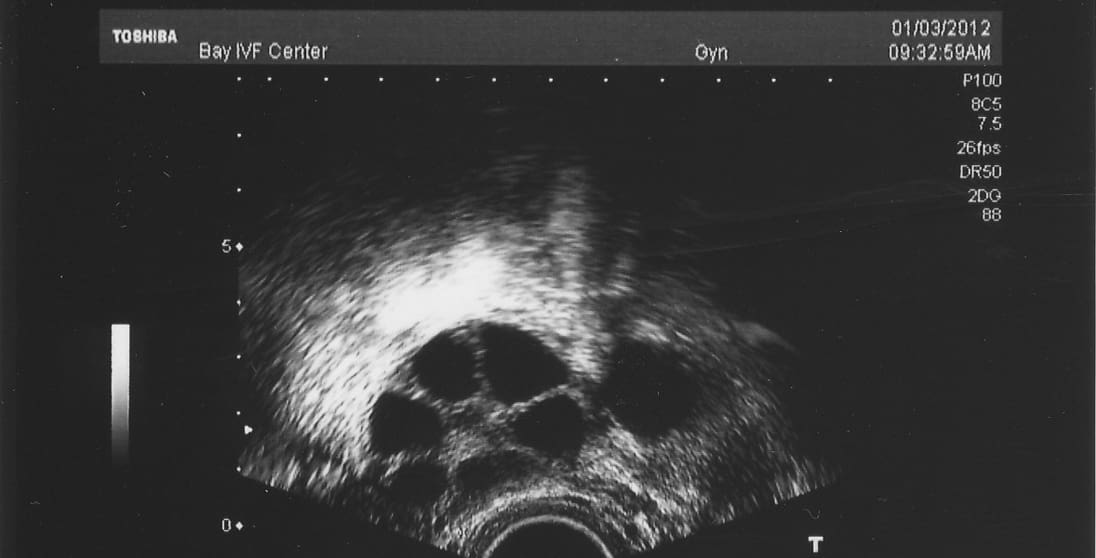

Ideally, IVF ovarian stimulation should lead to the development of 8 to 15 follicles and eggs. Having too few or too many follicles may result in suboptimal quality of the retrieved eggs.

Ovarian stimulation should lead to the development of several eggs in each ovary, as shown in the ultrasound image above. Each of the several follicles (dark circles) contains a microscopic egg.